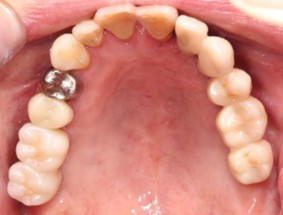

40代 女性

- リスク・副作用

- 術後疼痛、歯肉腫脹

- 治療の費用

- 合計¥686,000(税込)

【内訳】

インプラント(1本) ¥440,000

その他費用¥246,000

(薬・注射・レントゲン・CT・データ分析・骨造成・サージカルステント・血液検査) - 年齢/性別

- 40代/女性

- 患者の具体的な症状

- 左上6欠損のため義歯を使用していたが、噛むと痛みがあり不快なため、インプラント治療を希望

- 検査方法

- コーンビームCT、レントゲン撮影

- 診断結果

- 左下6欠損

- 治療詳細

- コーンビームCTによる画像診断で垂直的な骨高が不足し骨密度が少ないため、ソケットリフトによる骨再生治療とインプラント埋入を同時に行った。

- 通院回数

- 7回

- 治療期間

- 7か月